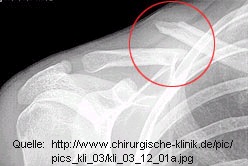

Diagnostik: Der Verletzte weiß bei einer anterioren Luxation meist sofort, daß sein Gelenk ”ausgekugelt” ist. Untrügbare Anzeichen hierfür sind nach einem typischen Unfallmechanismus insbesondere der plötzliche, überaus heftige Schmerz im Gelenkbereich, die sichtbare und tastbare Dislokation des Schlüsselbeinkopfes nach vorn oben (Abb. links) sowie die Bewegungseinschränkung im Schultergürtel. Bei einer posterioren Luxation muß die Verschiebung allerdings nicht sicht- oder tastbar sein; hier bringt meist erst eine Röntgen- oder CT-Untersuchung (Abb. rechts) Sicherheit.

Klavikulafraktur Eine der häufigsten Frakturen, besonders im Jugendalter. Pathogenese: Ein Sturz auf die Schulter oder die extendierte Hand führt zum Biegungsbruch im mittleren Drittel (indirekte Gewalt), Bruch im lateralen Drittel meist durch direkte Gewalt. Diagnose: Tastbare Unterbrechung der Klavikula. Fehlstellung der Fragmente: Das mediale Fragment steht durch Zug des M. sternocleidomastoideus nach kranial, das laterale durch das Armgewicht nach kaudal, häufig mit Verkürzung. (Abb. 44.5-2). Schmerzhafte Bewegungseinschränkung. Röntgenaufnahme in 2 Ebenen. Überprüfung des Pulses, der Sensibilität und Motorik! Therapie: Domäne der konservativen Behandlung. U.U. Reposition in Lokalanästhesie, Retention mit Rucksackverband (Abb. 44.5-3) durch Zug nach hinten für 3-4 Wochen. ...